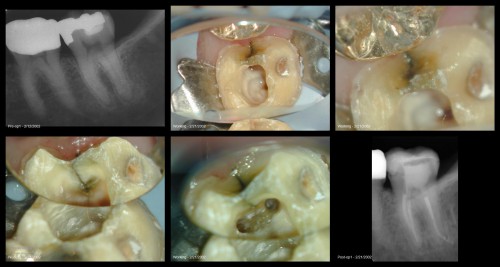

Tooth #31

By Gary Carr / July 11, 2018